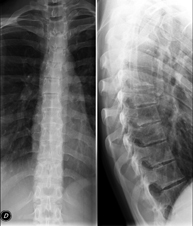

Tècnica que usa els raigs X a través de la qual s'obtenen imatges de la columna cervical per al seu estudi. Indicacions: traumatisme, dolor cervical. - RX Columna dorsal

Tècnica que usa els raigs X a través de la qual s'obtenen imatges de la columna dorsal per al seu estudi. Indicacions: traumatisme, mal d'esquena. - RX Columna lumbar

Tècnica que usa els raigs X a través de la qual s'obtenen imatges de la columna lumbar per al seu estudi. Indicacions: ciàtica, traumatisme, dolor lumbar. - RX Sacre-còccix

Tècnica que usa els raigs X a través de la qual s'obtenen imatges del sacre i del còccix per al seu estudi. Indicacions: traumatisme, dolor sacre o coccigi. - Telerradiologia columna

Tècnica que usa els raigs X a través de la qual s'obtenen imatges de tota la columna vertebral per al seu estudi, amb la valoració especialment de la presència d'escoliosi i dismetries pèlviques.